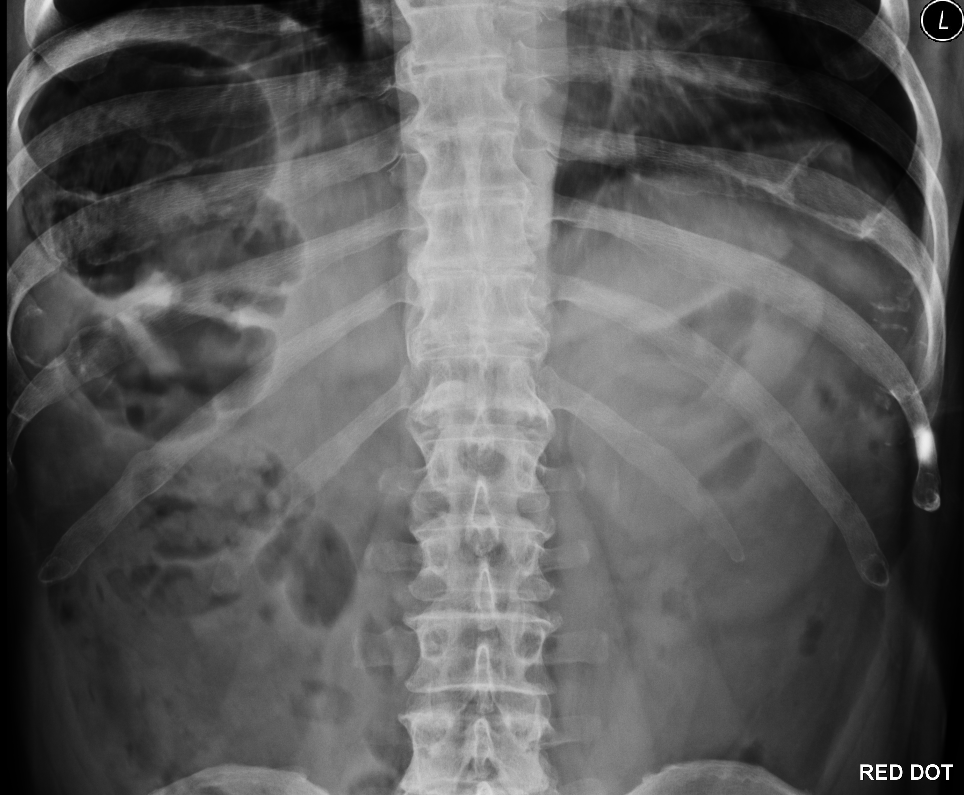

A 66-year-old presented with acute onset abdominal pain, vomiting and diarrhoea. The case was referred from ED to rule out obstruction due to the plain abdominal X-ray (pictured). It showed a discrete distended loop of bowel in the right upper quadrant with a diameter of 11cm, the rest of the abdomen was relatively featureless. Blood tests were in the normal range other than a mildly raised white cell count. Clinical examination of the abdomen was unremarkable, it was described as soft, nontender and nondistended. The patient was settled and comfortable having received analgesia in ED. Safety-netting advice was given, and the patient was discharged with an assumptive diagnosis of gastroenteritis.

The medical records, including previous abdominal scans and endoscopies, were reviewed. On a historic CT abdomen, the patient was noted to have high riding caecum. There should be a high index of suspicion for caecal volvulus as the X-ray features revealed a featureless pattern except for the distended caecum in the right upper quadrant, in a patient known to have a high-riding caecum. Although abdominal examination was benign, and the patient reported a misleading symptom (diarrhoea), it is important to appreciate the value of a plain abdominal X-ray. An early CT scan should have been considered.

Plain abdominal X-ray showing discrete distended bowel in the upper right quadrant. Pattern recognition is key